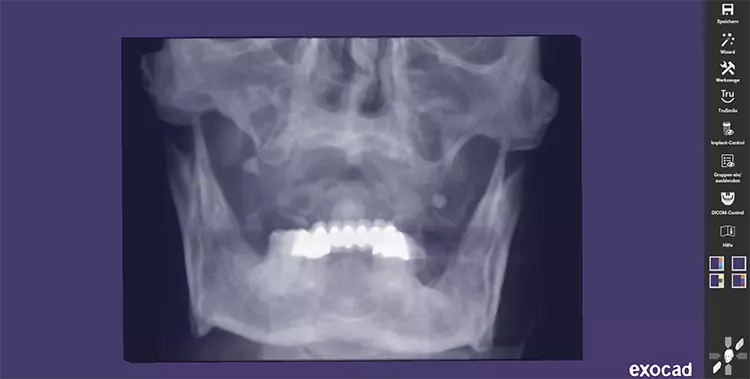

Nach einer Beratung und Aufklärung über Therapieoptionen und -alternativen wurde im gemeinsamen Konsens mit dem Patienten eine Pro-Arch-Sofortversorgung mittels Straumann® BLX im Oberkiefer geplant. Präoperativ wurde die Implantatversorgung mit Hilfe der dreidimensionalen Volumentomographie geplant (Abbildung 2). Die definitive Versorgung erfolgte in Zusammenarbeit mit den Kollegen der Prothetik in domo.

Der Patient wurde am gleichen Tag mit dem festsitzenden Brückenprovisorium entlassen und ausführlich über die Mundhygiene des Langzeitprovisoriums postoperativ aufgeklärt. Abbildung 8 zeigt eine regelrechte Implantatposition in der postoperativen Panoramaschichtaufnahme. In Abbildung 9 ist die postoperative Versorgung in situ zu sehen.